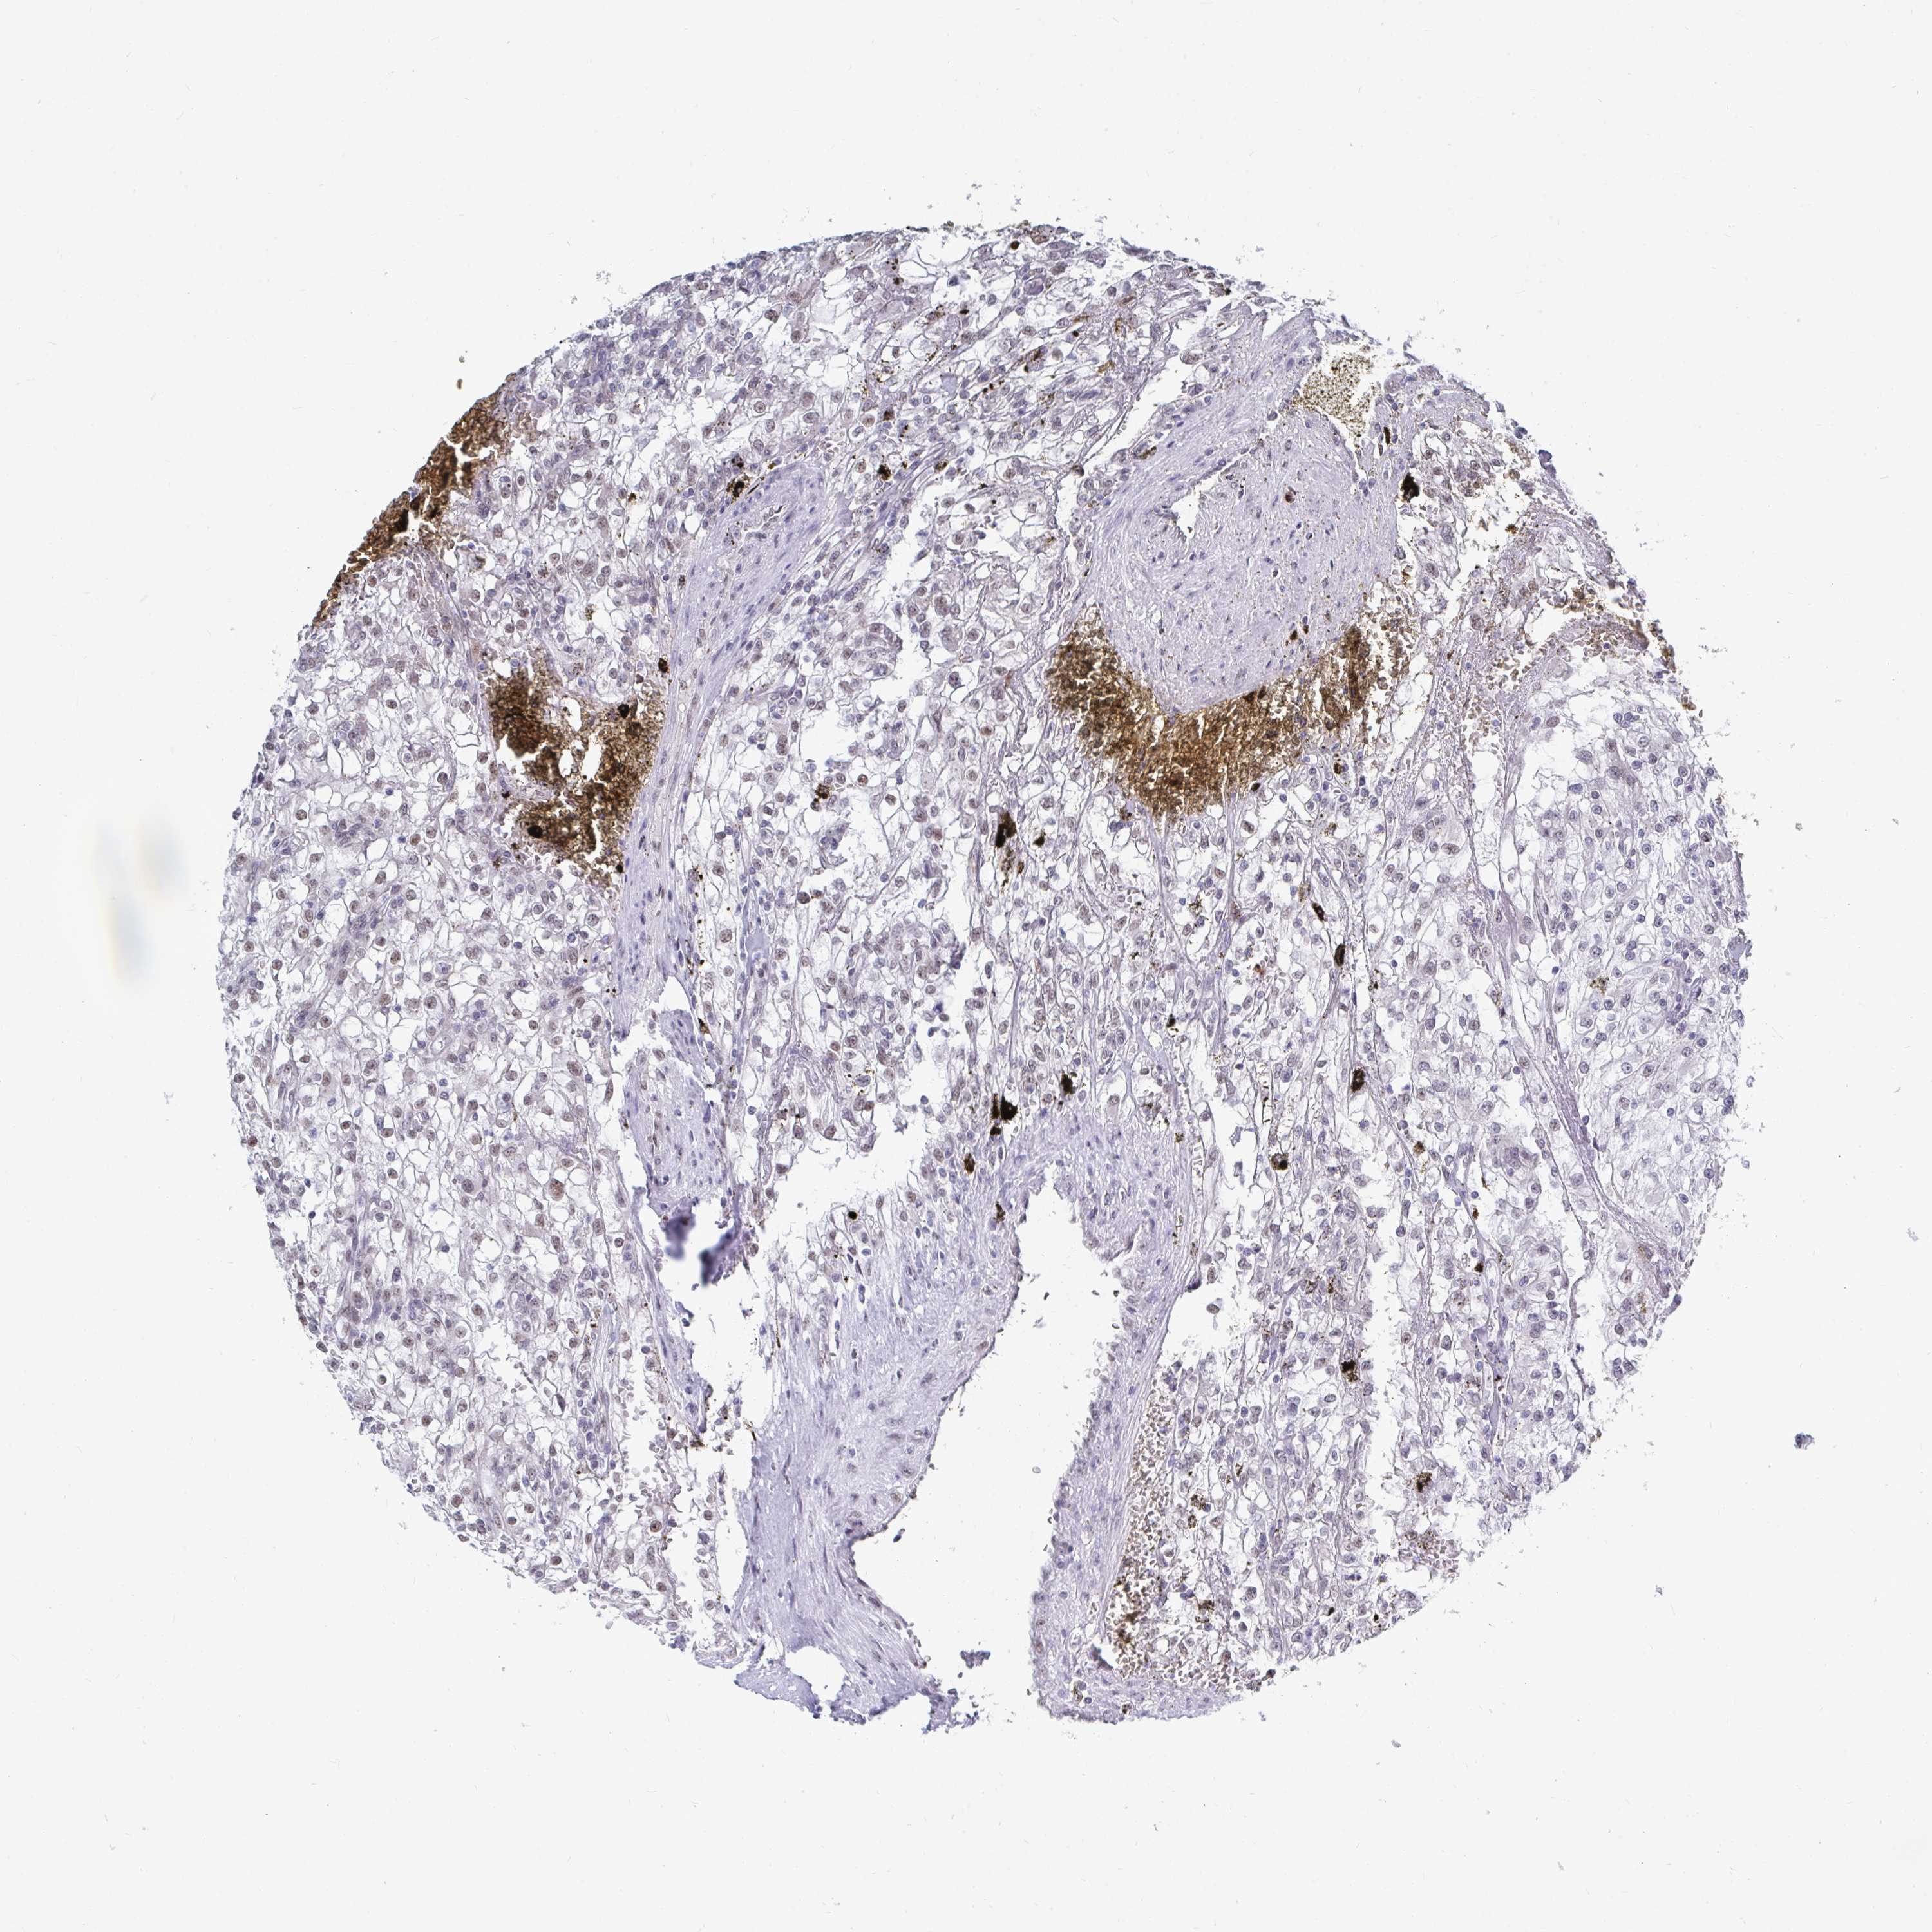

KIDNEY RENAL CLEAR CELL CARCINOMA (TCGA) - Interactive survival scatter ploti

The Survival Scatter plot shows the clinical status (i.e. dead or alive) for all individuals in the patient cohort, based on the same data that underlies the corresponding Kaplan-Meier plots. Patients that are alive at last time for follow-up are shown in blue and patients who have died during the study are shown in red.

The x-axis shows the expression levels (FPKM) of the investigated gene in the tumor tissue at the time of diagnosis. The y-axis shows the follow-up time after diagnosis (years). Both axes are complimented with kernel density curves demonstrating the data density over the axes. The top density plot shows the expression levels (FPKM) distribution among dead (red) and alive patients (blue). The right density plot shows the data density of the survived years of dead patients with high and low expression levels respectively, stratified using the cutoff indicated by the vertical dashed line through the Survival Scatter plot. This cutoff is automatically defined based on the FPKM cutoff that minimizes the p-score. The cutoff can be changed by dragging the vertical line or by entering a cutoff value in the square labeled "Current cut-off".

Under the Survival Scatter plot the p-score landscape (black curve; left axis) is shown together with dead median separation (red curve; right axis). Dead median separation is the difference in median mRNA expression between patients who have died with high and low expression, respectively. It is calculated as follows: median FPKM expression of dead patients with high expression - median FPKM expression of dead patients with low expression. This is intended to aid the user in visually exploring custom cutoffs and the associated p-scores and dead median separation.

Individual patient data is displayed and can be filtered by clicking on one or more of the category buttons on the top of the page. Categories describing expression level and patient information include: high, low, alive, dead, female, male and tumor stages. The scale of the x-axis can be toggled between linear and log-scale by clicking on the "x log" button. Mouse-over function shows TCGA ID, patient information and mRNA expression (FPKM) for each patient.

& Survival analysisi

Kaplan-Meier plots summarize results from analysis of correlation between mRNA expression level and patient survival. Patients were divided based on level of expression into one of the two groups "low" (under cut off) or "high" (over cut off). X-axis shows time for survival (years) and y-axis shows the probability of survival, where 1.0 corresponds to 100 percent.

TRIP12 is potential prognostic, high expression is favorable in Kidney Renal Clear Cell Carcinoma (TCGA)

Best expression cut offi

Based on the FPKM value of each gene, patients were classified into two groups and association between prognosis (survival) and gene expression (FPKM) was examined. The best expression cut-off refers the FPKM value that yields maximal difference with regard to survival between the two groups at the lowest log-rank P-value. Best expression cut-off was selected based on survival analysis .

When clicking on this number, the vertical dashed line indicating cut-off, the interactive survival plot, and the Kaplan-Meier curve will be adjusted to show results based on the best expression cut-off.

: 31.45

P scorei

Log-rank P value for Kaplan-Meier plot showing results from analysis of correlation between mRNA expression level and patient survival.

N/A

TCGA RNA samplesi

RNA-seq data is reported as average FPKM (number Fragments Per Kilobase of exon per Million reads), generated by the The Cancer Genome Atlas (TCGA) .

Normal distribution across the dataset is visualized with box plots, shown as median and 25th and 75th percentiles. Points are displayed as outliers if they are above or below 1.5 times the interquartile range. FPKM values of the individual samples are presented next to the box plot.

Average pTPM 46.4

Number of samples 521